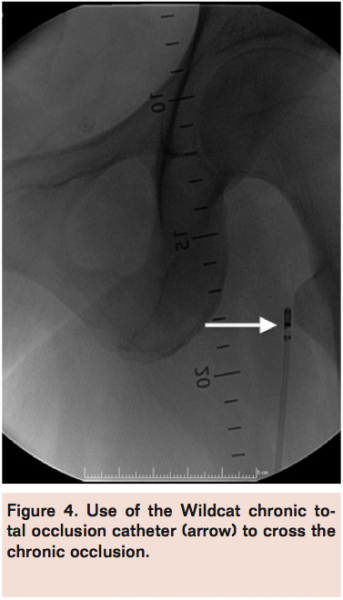

A Wildcat chronic total occlusion catheter (Avinger) was advanced in active and passive modes to traverse the occlusion (Figure 4) followed by a glidewire (Terumo) with confirmation of intraluminal position within the IVC via contrast injection (Figure 5). Serial balloon venoplasty was performed in ascending fashion using EverCross 6 mm x 100 mm, 7 mm x 120 mm, and 12 mm x 60 mm balloons (Covidien) and subsequent stenting with Protégé Everflex 12 mm x 80 mm and 8 mm x 150 mm self-expanding stents (Covidien) in overlapping fashion from the ostium of the left common iliac vein (Figure 6) to the common femoral vein. The entire stented segment was post-dilated with the EverCross 12 mm x 60 mm balloon and final venography demonstrated brisk flow through the left common femoral to common iliac vein stent (Figure 7).

There is increasing evidence that early recognition and invasive treatment of DVT can reduce the incidence of PTS. In the acute setting of DVT, catheter-directed thrombolysis has been shown to be efficacious with low risk of bleeding for patients with high proximal DVT.11 Pharmacomechanical thrombectomy offers a safe and effective alternative for treatment of acute DVT,12 although limited by age of clot when greater than 3 days old.13 In chronic DVT, standard endovascular chronic total occlusion revascularization techniques are employed to traverse the occlusion. The Wildcat catheter has previously been reported for use in crossing a chronic venous stent occlusion14 and was used successfully in this case as the first reported use of the device in de novo venous occlusion. Subsequent endovenous angioplasty combined with stenting has been demonstrated as a safe and effective treatment strategy with good long-term patency rates.15